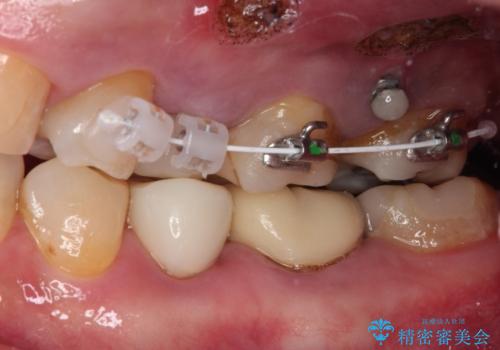

- 奥歯の詰め物が外れてしまったとのことで来院された患者様です。

レントゲン写真より、既に根管治療がされている歯であり、根尖部に骨透過像が認められました。

特に症状はありませんでしたが、根管治療を希望されたため、まずは根管治療を行うこととしました。

根管治療の際に、咬み合う上顎の銀歯が内側に入り込んでいることも気になるとのことであったため、部分矯正を行い、その後上下を同時に補綴治療することとしました。